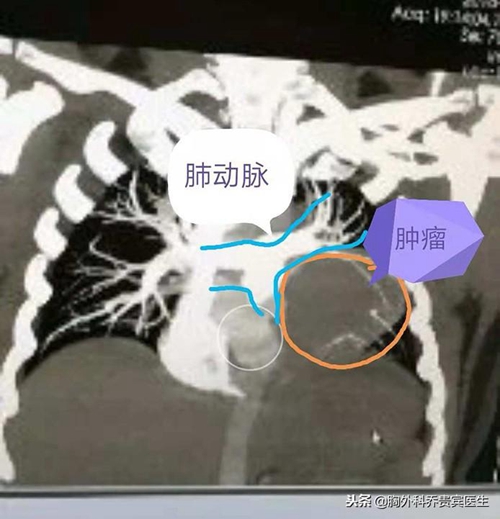

可是,女孩没有想到的是,肿瘤的生长超出预期,最近两周突然出现睁不开眼的情况。再次就医,医生告诉她,这应该是胸腺瘤生长造成的重症肌无力。再次检查,发现肿瘤较8月份明显长大, 同时发现肿瘤压迫了心脏大血管和肺组织。

从手术本身来考虑,这个手术风险很高,一是在肿瘤切除的时候可能造成大出血,下不了台;另一方面,由于肿瘤和周围脏器生长密切,不一定能完整切除。

手术中发现肿瘤侵犯了肺动脉外膜,对肺也有侵犯,经过2个多小时的仔细剥离,终于完整切除了肿瘤,同时,还切除了部分心包和受侵犯的肺组织。